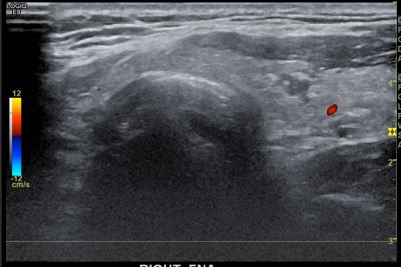

상기환자  외부검사이상소견으로 내원하신 20대 후반 남성분으로 의심스러운 갑상선 우엽결절 세포검사진행후 갑상선암으로 진단되었습니다